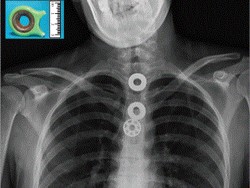

Foto Rontgen Ini Tunjukkan yang Terjadi Bila Menelan Fidget Spinner

Diduga karena depresi, seorang remaja memutuskan untuk menelan bagian mainan fidget spinner. Hasilnya ia pun tersedak hingga butuh bantuan dokter.